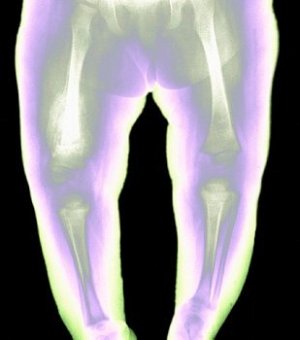

Для рахитичных детей характерны следующие визуальные симптомы:

- «икс-образные ноги»;

- Период разгара. На этой стадии костная система претерпевает изменения — форма головы стает ассиметричной, уплощается затылок, лобная кость увеличивается. Происходит деформация грудной клетки, нижних конечностей. Уже достаточно выражены нарушения физического и психического развития.